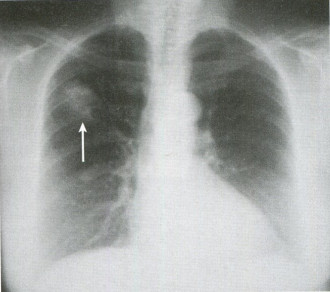

3일간 약을 복용한 후 기침은 어느 정도 완화되었으나 여전히 오른쪽 가슴 통증이 지속되어 드물긴 하지만 기침 시 갈비뼈 골절이 유발될 수 있어 갈비뼈 X선을 촬영하였습니다.

갈비뼈 X선에서는 골절 등 이상 소견이 없었으나 흉통이 호전되지 않고 지속되고 있으며 X선에서는 잘 확인되지 않는 미세 골절 여부를 확인하기 위해 갈비뼈 초음파를 실시하였습니다.

▶ 진단 흉부 엑스레이 – 가장 기본적으로 할 수 있는 검사 방법, 미세 골절의 경우 엑스레이로 확인하기 어려운 초음파 검사 – 엑스레이 검사상 골절 소견이 관찰되지 않을 경우 갈비뼈 골절 진단에 사용 가능.미세 골절 확인 및 주변 장기 손상을 확인할 수 있다는 장점이 있다.뼈 주사 검사, 흉부 CT-X선 검사상 확인되지 않은 골절 감별로 사용 가능.